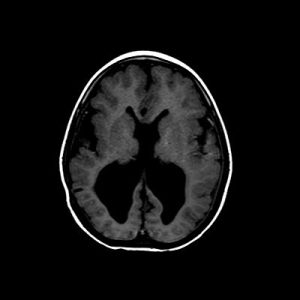

📣📣📣Haftanın ödüllü olgu sorusu yayınlandı.

Yanıtlarınızı www.tnrd.org.tr adresinden bekliyoruz.